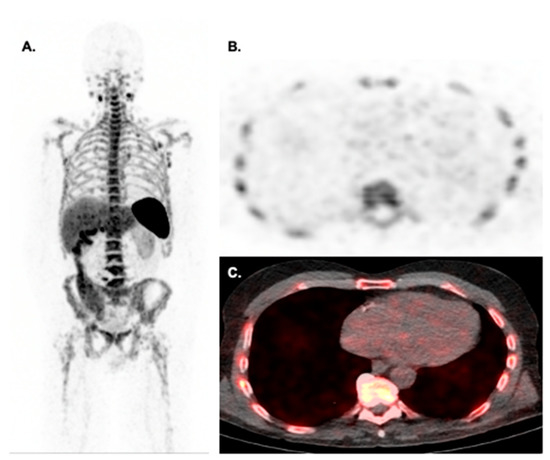

- Bauckneht, M.; Ferrarazzo, G.; Fiz, F.; Morbelli, S.; Sarocchi, M.; Pastorino, F.; Ghidella, A.; Pomposelli, E.; Miglino, M.; Ameri, P.; et al. Doxorubicin Effect on Myocardial Metabolism as a Prerequisite for Subsequent Development of Cardiac Toxicity: A Translational 18F-FDG PET/CT Observation. J. Nucl. Med. Off. Publ. Soc. Nucl. Med. 2017, 58, 1638–1645. [Google Scholar] [CrossRef]

- Sarocchi, M.; Bauckneht, M.; Arboscello, E.; Capitanio, S.; Marini, C.; Morbelli, S.; Miglino, M.; Congiu, A.G.; Ghigliotti, G.; Balbi, M.; et al. An increase in myocardial 18-fluorodeoxyglucose uptake is associated with left ventricular ejection fraction decline in Hodgkin lymphoma patients treated with anthracycline. J. Transl. Med. 2018, 16, 295. [Google Scholar] [CrossRef]